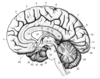

Key gyri on medial view of frontal lobe

Superior frontal gyrus

Paracentral lobule

Cingulate gyrus

Key sulci on medial surface of frontal lobe

Cingulate sulcus

Key gyri on orbital view of frontal lobe

Gyrus rectus

Medial orbital gyrus

Anterior orbital gyrus

Posterior orbital gyrus

Lateral orbital gyrus

Key sulci on orbital surface of frontal lobe

Olfactory sulcus

Orbital sulcus